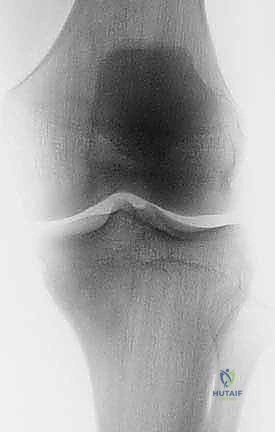

يُعد استئصال الظنبوب القريب بالطرف الصناعي إجراءً جراحياً متقدماً ومعقداً للغاية، يتضمن إزالة دقيقة للجزء العلوي من عظم الساق (الظنبوب) المصاب بورم خبيث، أو ورم حميد عدواني، أو تلف مفصلي مدمر لا يمكن إصلاحه بالطرق التقليدية. بعد الاستئصال الآمن للورم مع حواف أمان سليمة، يقوم الجراح باستبدال العظم والمفصل المفقود بطرف صناعي معدني متطور (مصنوع غالباً من التيتانيوم وسبائك الكوبالت والكروم) لاستعادة وظيفة الركبة والطرف السفلي، مما يتيح للمريض العودة إلى ممارسة حياته الطبيعية والمشي على قدميه مجدداً.

تُعتبر منطقة الظنبوب القريب (Proximal Tibia) واحدة من أكثر المواقع التشريحية تحدياً في جراحات العظام والأورام. يعود هذا التعقيد إلى عدة عوامل: قربها الشديد من حزمة الأوعية الدموية والأعصاب الرئيسية التي تغذي الساق والقدم، ونقص التغطية العضلية الكافية في الجزء الأمامي من الساق، بالإضافة إلى الدور الحيوي الذي يلعبه هذا الجزء في آلية تمديد الركبة (Extensor Mechanism) وتحمل وزن الجسم بالكامل. لذلك، فإن نجاح هذه الجراحة لا يعتمد فقط على المعدات الحديثة، بل يعتمد بشكل أساسي وحاسم على مهارة الجراح وخبرته الاستثنائية.

لفهم مدى تعقيد وعبقرية جراحة استئصال الظنبوب القريب، من الضروري الإبحار في أعماق التشريح الأساسي لهذه المنطقة الحيوية. لا يقتصر الأمر على مجرد عظام، بل هو نظام هندسي وبيولوجي متكامل ومعقد. يتكون مفصل الركبة من التقاء عظم الفخذ (Femur) من الأعلى، وعظم الساق أو الظنبوب (Tibia) من الأسفل، وعظم الشظية (Fibula) الجانبي، بالإضافة إلى الرضفة أو صابونة الركبة (Patella) في الأمام. الجزء القريب من الظنبوب هو الجزء العلوي العريض من عظم الساق، والذي يشكل القاعدة الأساسية التي يستند عليها مفصل الركبة ويتحمل وزن الجسم بأكمله.